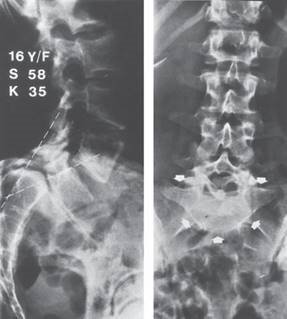

What is the name of the spinal deformity in the photograph above?

This is idiopathic scoliosis.

At what age and in which sex does it most commonly present?

I t is commonest in girls and often presents around adolescence. The thoracic curve is usually right sided. The prevalence is around 3 % of the population, although less than 10 % of curves need treatment.

What factors aff ect progression of the deformity?

1 . The future growth potential of the patient, i.e. the level of skeletal maturity at the time of diagnosis. This is measured by the Risser stage: z Risser 0 = no ossification of the iliac epiphysis z Risser 1 = 0โ25 % ossification z Risser 2 = 25โ50 % ossification z Risser 3 = 50โ75 % ossification z Risser 4 = 75โ100 % ossification z Risser 5 = fused epiphysis

2. The curve magnitude at the time of diagnosis:

z Curves of <30 ยฐ at maturity are unlikely to progress z Curves of 30โ50 ยฐ at maturity are likely to progress another 10โ15 ยฐ z Curves of > 50 ยฐ at maturity are likely to progress at around 1 ยฐ /year

3. Sex: curves in females are more likely to progress 4. Curve type: double curves are more likely to progress

How is it classifi ed?

There are two common classifi cation systems.

King and Moe describe Types 1โ5 depending on the shape of the curve:

z Type1: S-shaped double curve where the lumbar curve is larger or less flexible z Type 2: S-shaped double curve where the thoracic curve is larger or less flexible z Type 3: single thoracic curves z Type 4: long thoracic curves where L4 is tilted into the curve z Type 5: double thoracic curve where T1 is tilted into the thoracic curve

The more complex Lemke classifi cation system describes the curve type (1โ6) and adds a modifi er (A, B, or C) depending on where the lumbar curve is in relation to central sacral vertical line, and another modifi er (โ, N, or + ) based on the thoracic sagittal profi le.